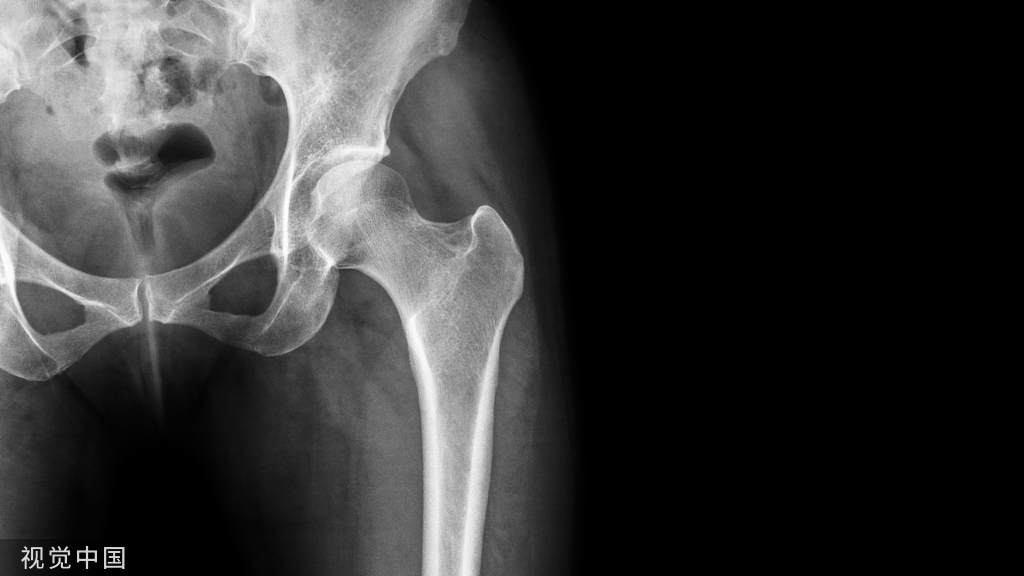

髋臼的解剖、生物力学与受伤机制!